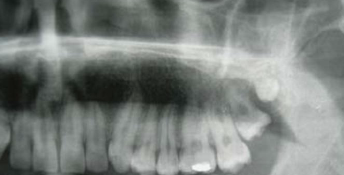

DGI radiographic presentation

bulbous crown, cervical constriction, pulp obliteration varies, expanded pulp = shell teeth